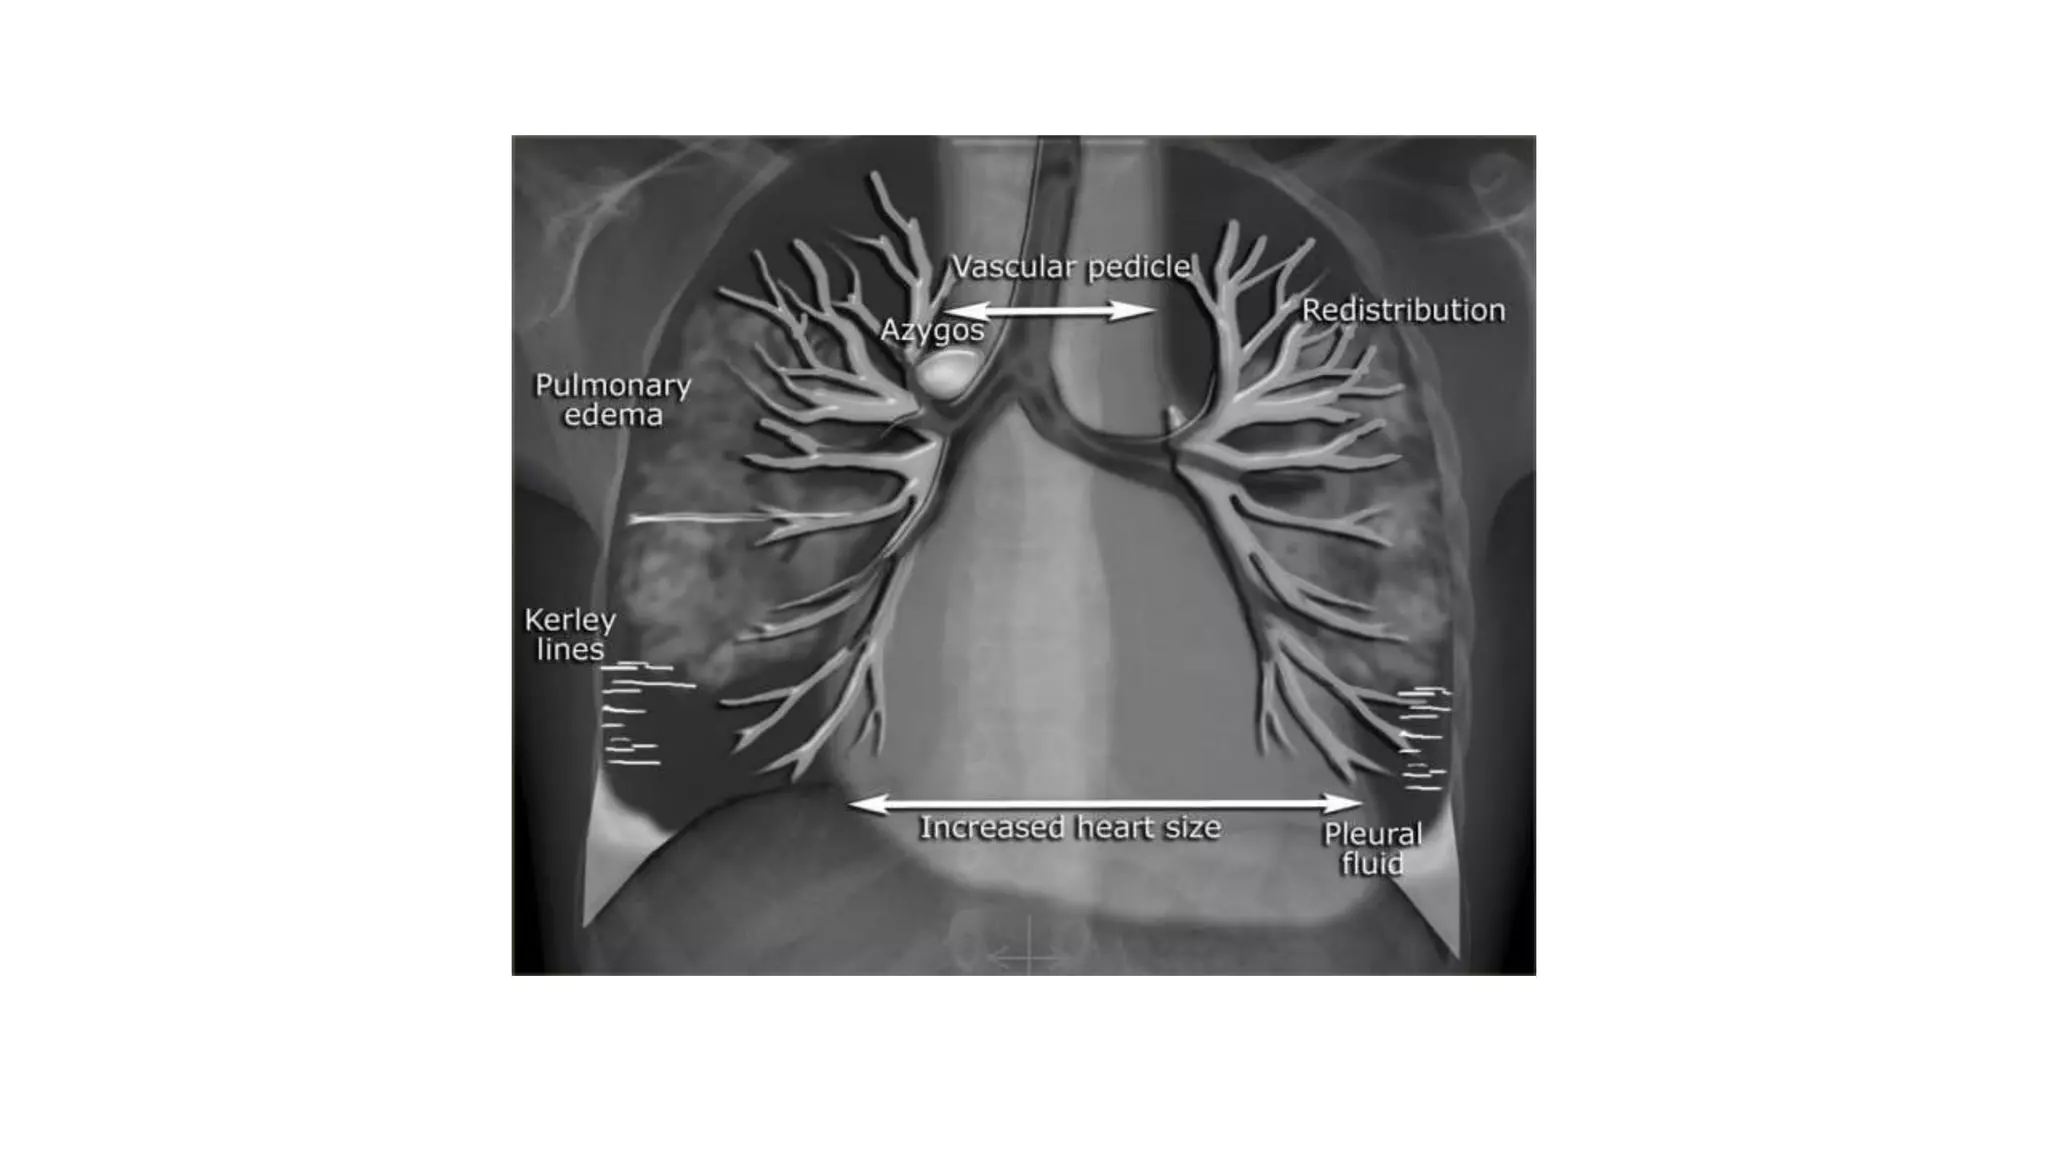

A chest x-ray is obtained to determine the size, contour, and

position of the heart.

It reveals cardiac and pericardial calcifications and demonstrates

physiologic alterations in the pulmonary circulation.

Although it does not help diagnose acute MI, it can help diagnose

some complications (eg, HF).

Correct placement of pacemakers and pulmonary artery

catheters is also confirmed by chest x-ray.

A chest x-rayis obtained to determine the size, contour, and position of the heart. It reveals cardiac and pericardial calcifications and demonstrates physiologic alterations in the pulmonary circulation. Although it does not help diagnose acute MI, it can help diagnose some complications (eg, HF). Correct placement of pacemakers and pulmonary artery catheters is also confirmed by chest x-ray.